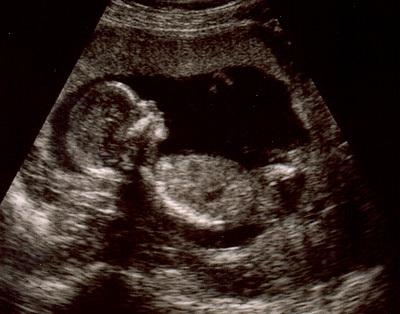

УЗИ демонстрирует плод, у которого размеры головы соответствуют размерам туловища. Это является нормальным явлением. На этой неделе плод увеличился вдвое по сравнению с предыдущей. Теперь пальцы уже не соединены перепонками, и на качественном аппарате их можно будет даже пересчитать. Начинают формироваться радужные оболочки глаз. На голове плода появляются фолликулы волос, а на руках и ногах — ногти. У девочек также развиваются яичники. Уши, нос, небо и язык полностью сформированы.